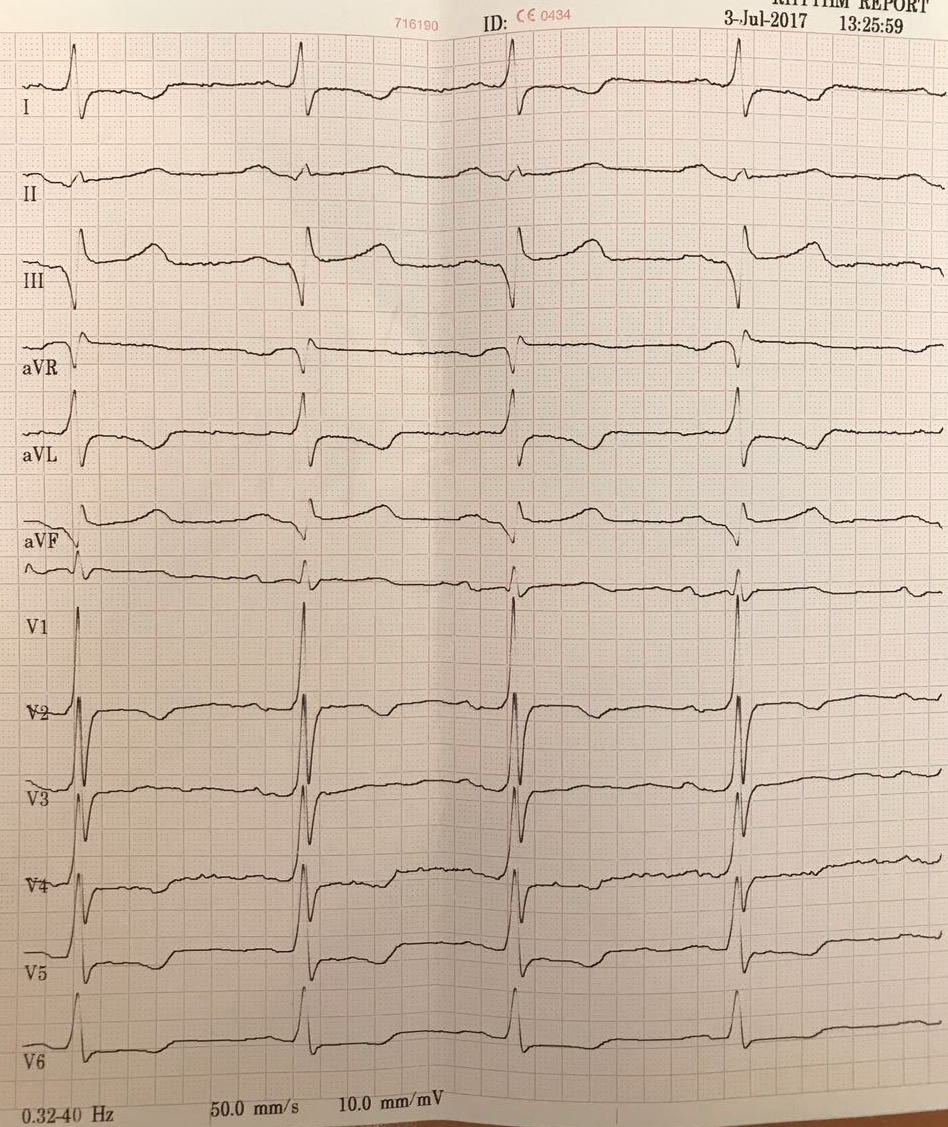

Изображение

Особенность работы оптимайзера, он работает не постоянно

Оптимайзер. Когда включен и когда выключен